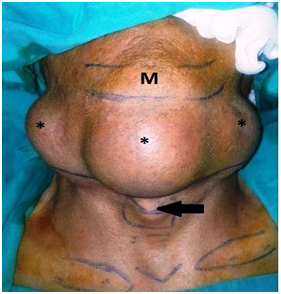

Sixty eight years old male patient was admitted to our clinic with the complaints of progressive swelling on neck which causes speech difficulty. He couldn’t close his mouth properly (Figures 1&2). It was learnt that he was only drinking fluids but could not eat solid meals for long years. In his physical examination, a mass lesion fulfilling mouth base and all oral cavity pushing the tongue to the posterior was observed. This mass was filling all submental and submandibular regions bilaterally on neck and it were running over the secondary regions. The mass was soft in palpation and was approximately 20x10cm in dimensions. The patient’s tongue movements could not be detected due to size of the mass but his flexible endoscopic examination and other ear- nose- throat examinations were normal. In magnetic resonance imaging (MRI), a conglomerated, highly contrast enhanced mass lesion with an approximately 20 cm diameter that was narrowing the upper airways, considerably widespread on submental region, at the 2nd region level on bilateral parotid and submandibular regions was detected (Figure 3).

Figure 1 Preoperative appearance of the patient. White Arrow: Tongue; Black Arrow: Mass (Mass is fulfilling the oral cavity completely).

Figure 2 Preoperative appearance of the patient. black arrow, larynx, m, mentum, mass.